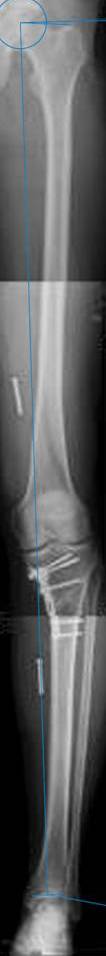

картинки оперированного пациента 40 лет, травма в 2006 году.

оперирован 06.11.2009г - корригирующая остеотомия большеберцовой кости.

Согласен с Вами, эта "скажем" не высокая остеотомия

нужно было выше.....

Я картинку собрал с некоторыми погрешностями, если провести отвес от центра вращения головки бедра до середины голени (на пациенте),то имеется небольшой вальгус (гиперкоррекция)конечно она (гиперкоррекция) не достигает 10 гр, но 5 гр она достигает.

К сожалению, не очень удачный пример. Если верить Р-граммам, имеет место быть дисплазия мыщелков бедренной кости с наклоном суставной линии. Это уже создает сложности получения хороших отдаленных результатов. Кроме того, по классике, необходима гиперкоррекция с созданием вальгуса 7-10 градусов для максимальной разгрузки медиального отдела КС. Если верить укладке, то линия сустава имеет четкий варусный наклон, поэтому результат операции м.б. кратковременным. В этих случаях показана двойная остеотомия бедра и тибии.

Если сделать правильно, то видно, что бедренная кость в порядке, а цель остеотомии (низкой, кстати), не достигнута вовсе.

Сохраняется варус. Для того, чтобы создать вальгусную гиперкоррекцию, не моделируя при этом откровенный Х голени, можно сделать медиализирующую остеотомию.